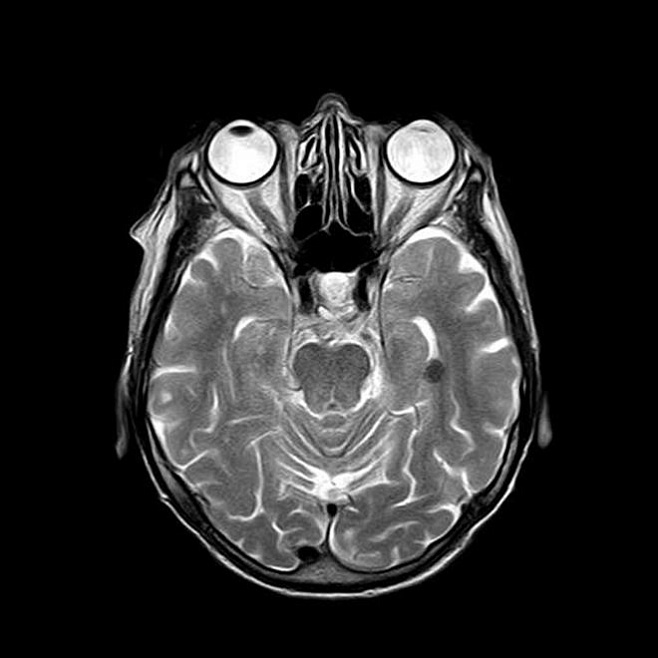

Кули и ее коллеги разработали и протестировали портативный прототип сканера для выполнения МРТ мозга, который можно подключать к обычной розетке и который издает гораздо меньше шума, чем традиционные МРТ-сканеры. Сам магнит имеет размер не больше бельевой корзины, а общий вес всей системы – 230 кг (при этом его можно снизить до 160 кг, если заменить типовые компоненты оборудования на легковесные и сделанные на заказ). В ходе тестирования с участием троих здоровых взрослых МРТ-сканер смог сделать 3D-снимки мозга за 10 минут.